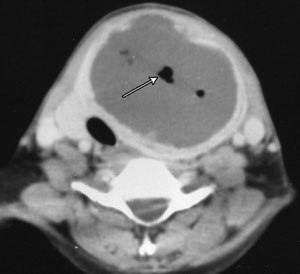

A 40-year-old woman presented with sudden onset of a painful neck swelling, fever and dysphagia. Examination revealed a warm, tender lump in her thyroid gland. Five weeks previously, she had had an abdominal hysterectomy with bilateral salpingo-oophorectomy for pelvic inflammatory disease. There was no evidence of leukopenia or diabetes. Computed tomography and x-ray images were consistent with a diagnosis of thyroid abscess (Figure 1 and Figure 2).